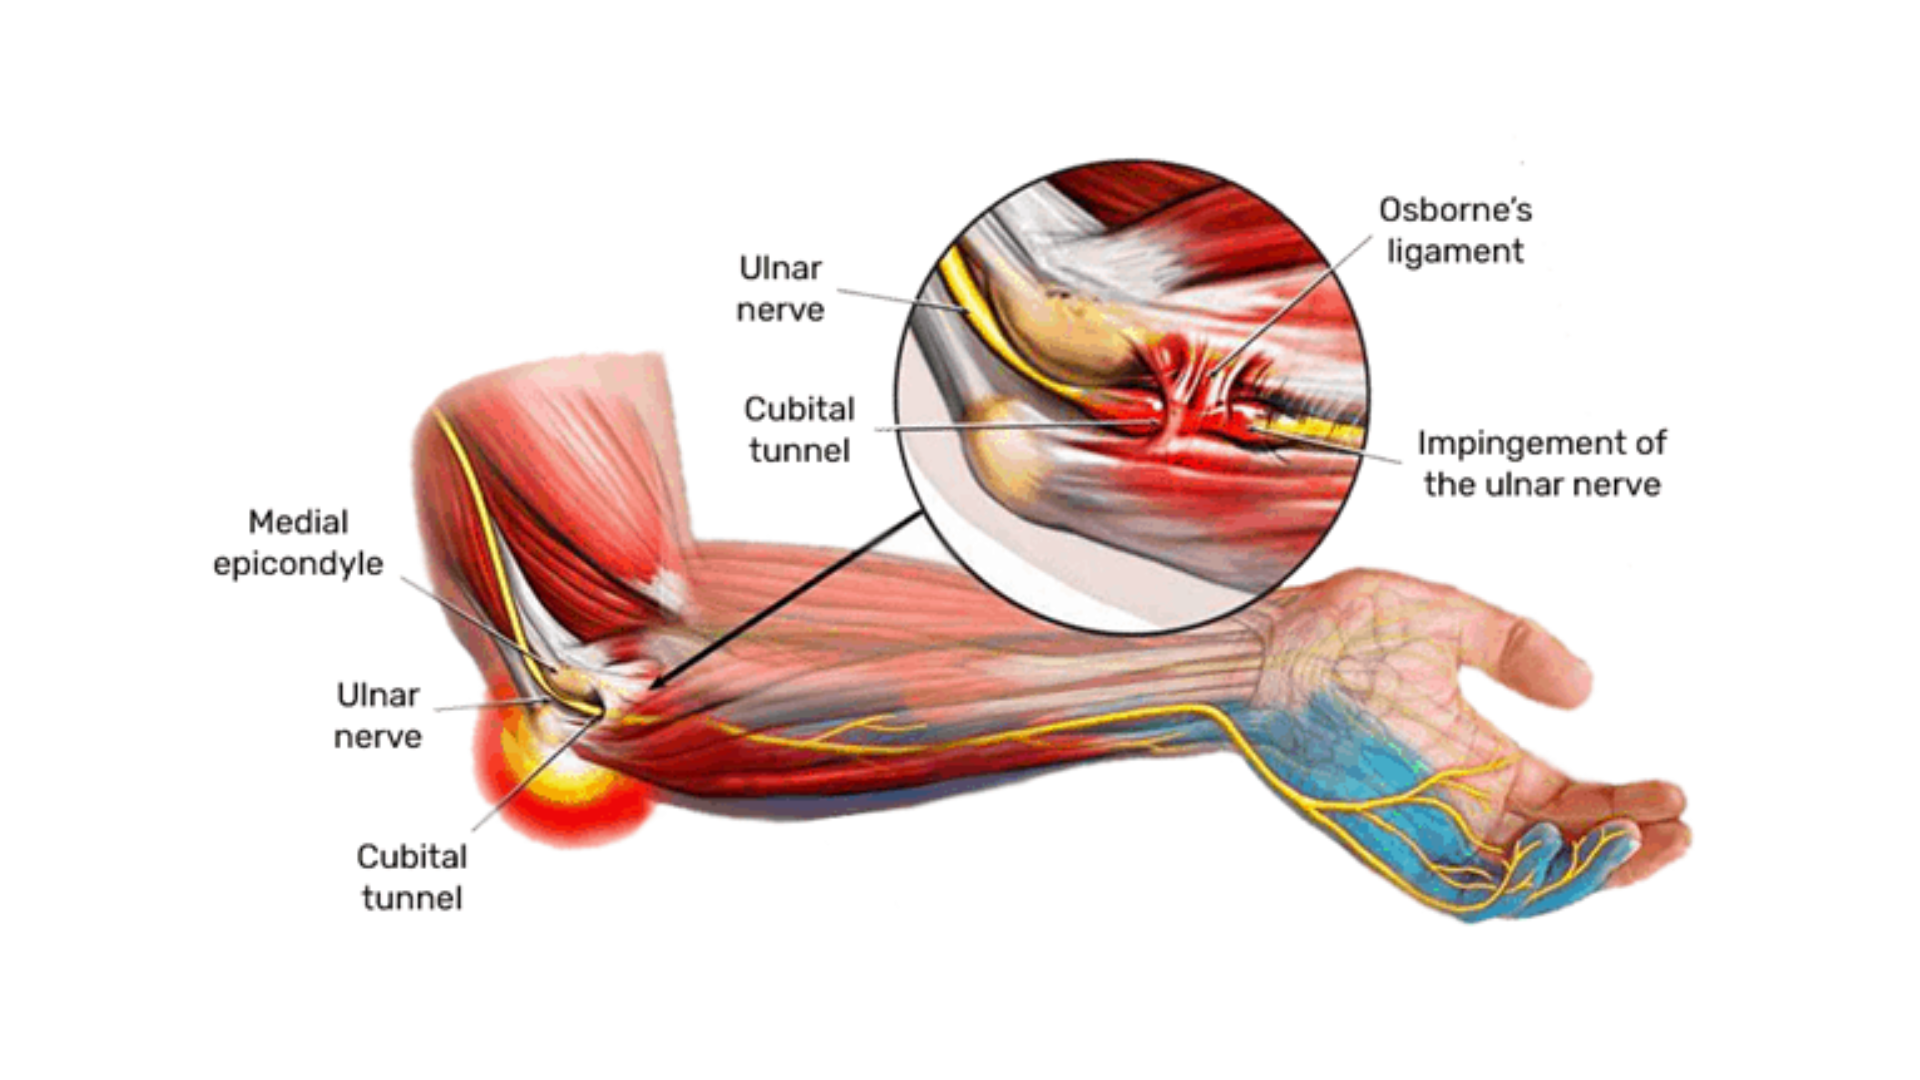

Explore videos and articles about the elbow. Whether you’re experiencing discomfort due to tennis elbow, fractures, or other conditions relating to elbow pain, our informative guide provides insights into causes, symptoms, and effective treatments to alleviate your pain. Explore a range of therapeutic approaches, from physical therapy exercises to innovative medical interventions, tailored to aid in your recovery and restore functionality from elbow ailments.

Dive into a diverse range of insightful pieces crafted by experts in the field, covering everything from common ailments like tennis elbow to more complex conditions. Unravel the intricacies of elbow pain, anatomy, understand symptoms, and discover innovative treatment options. Whether you’re a patient seeking clarity or a medical professional seeking in-depth knowledge, our collection caters to all levels of curiosity and expertise.